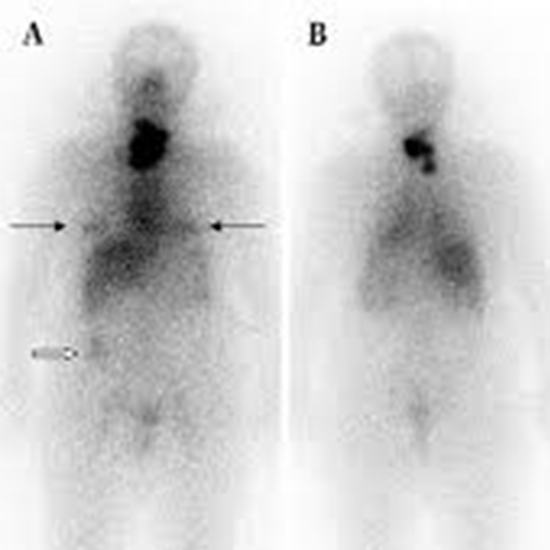

Radioactive iodine uptake test Wikipedia shop, Radioactive iodine uptake Information Mount Sinai New York shop, Radioactive Iodine Uptake Test shop, Radioactive Iodine Uptake Testing Background Indications shop, Radioactive Iodine Uptake Test Risks Preparation and Results shop, Radioactive Iodine Uptake And Scan My Endo Consult shop, Radioactive Iodine Columbia Surgery shop, Radioactive Iodine Uptake Test MEDizzy shop, Radioactive Iodine RAI Uptake THANC Guide shop, A radioactive iodine uptake test A B C and D demonstrate shop, StudyXing Medicine on X shop, Radioactive iodine uptake RAIU test shows large right and left shop, Radioactive Iodine Therapy to Treat Thyroid Cancer shop, AMBOSS Step2CK quiz time Can you distinguish the shop, Thyroid Scintiscanning an overview ScienceDirect Topics shop, Hyperthyroidism and Thyrotoxicosis Workup Approach Considerations shop, Radioactive Iodine Uptake Test Health Library NewYork Presbyterian shop, Twenty four hour radioactive iodine 123 uptake test. The images shop, Graves Disease Endocrine Medbullets Step 2 3 shop, Radioactive Iodine Uptake Testing Background Indications shop, Radioactive Iodine Uptake Test Risks Preparation and Results shop, Hyperthyroidism Diagnosis and Treatment AAFP shop, Thyroid Cancer SNMMI shop, Radioactive Iodine RAI Uptake THANC Guide shop, Thyroid Scan and Uptake shop, Determination of remnant thyroid volume comparison of shop, Solved Radioactive iodine uptake Normal adult 16 yr. old Chegg shop, Radioactive Iodine Uptake and Scan in Various Forms of shop, Radioactive iodine uptake shop, RADIOACTIVE IODINE UPTAKE TEST Text in List. Doctor Looking for shop, Thyroid Scan and Uptake RadiologyInfo shop, Radioactive iodine uptake shop, Thyroid Scan in Bangalore Nuclear Scan Manipal Hospitals shop, PatEdu Thyroid Surgery shop, Iodine Whole Body Scan Test Price In Delhi Cost Near Me India shop.

Radioactive Iodine Uptake Testing Background Indications